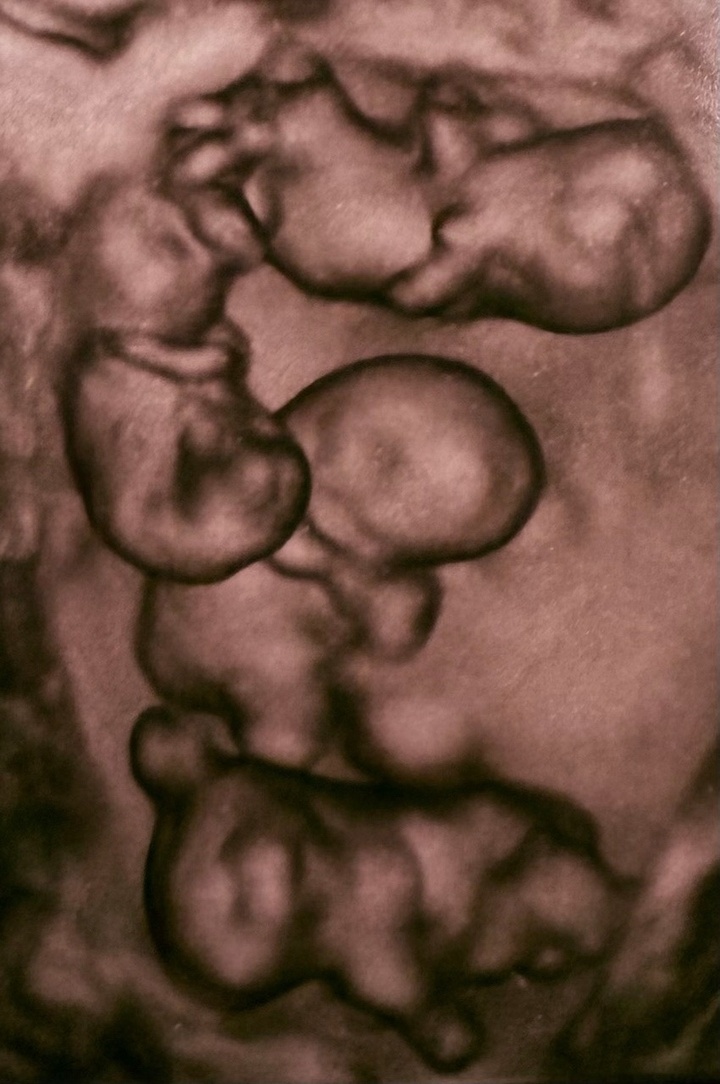

Фото: пресс-служба Родильного дома № 17 в Санкт-Петербурге.

Как сообщили в родильном доме, на сроке 32 недели на свет появились четыре сестры весом от 1360 до 1640 граммов. По медицинской статистике, вероятность рождения монохориальной четверни — около одного случая на 15,5 миллиона родов. Операцию провела команда под руководством главного врача, доктора медицинских наук, профессора Антона Михайлова. Заместитель главврача родильного дома №10, профессор Евгений Михайлин, курировал пациентку как консультант-гематолог.